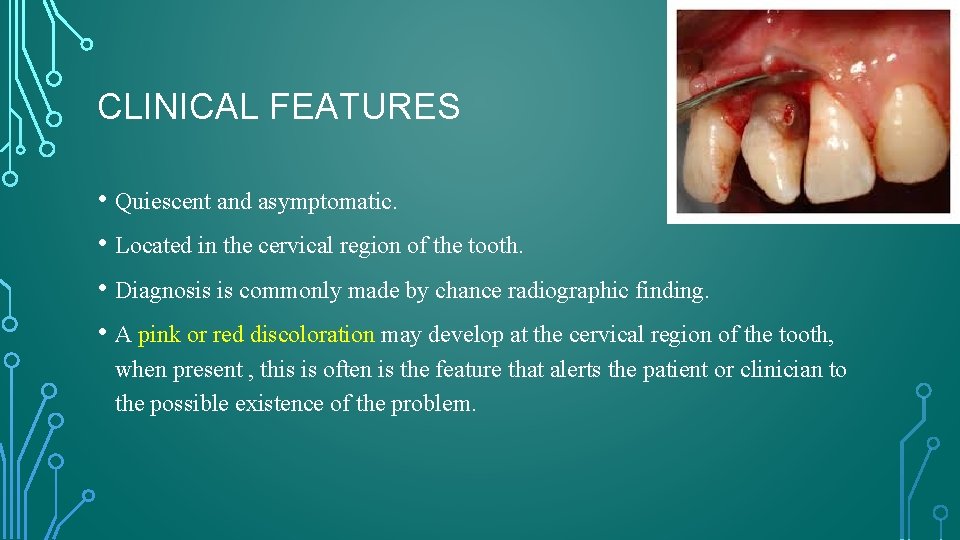

CLINICAL FEATURES • Quiescent and asymptomatic. • Located in the cervical region of the tooth. • Diagnosis is commonly made by chance radiographic finding. • A pink or red discoloration may develop at the cervical region of the tooth, when present , this is often is the feature that alerts the patient or clinician to the possible existence of the problem.

• Discoloration is due to the fibrovascular granulation tissue occupying the resorptive defect. • Loss of periodontal attachment may occur in the region of the resorption , and probing of the resorptive defect or the associated periodontal pocket causes the granulation tissue to bleed profusely.

• As the process progresses, perforation of the root canal wall and bacterial contamination of the pulp may occur. • The affected tooth may develop pulpitis and the associated clinical symptoms.